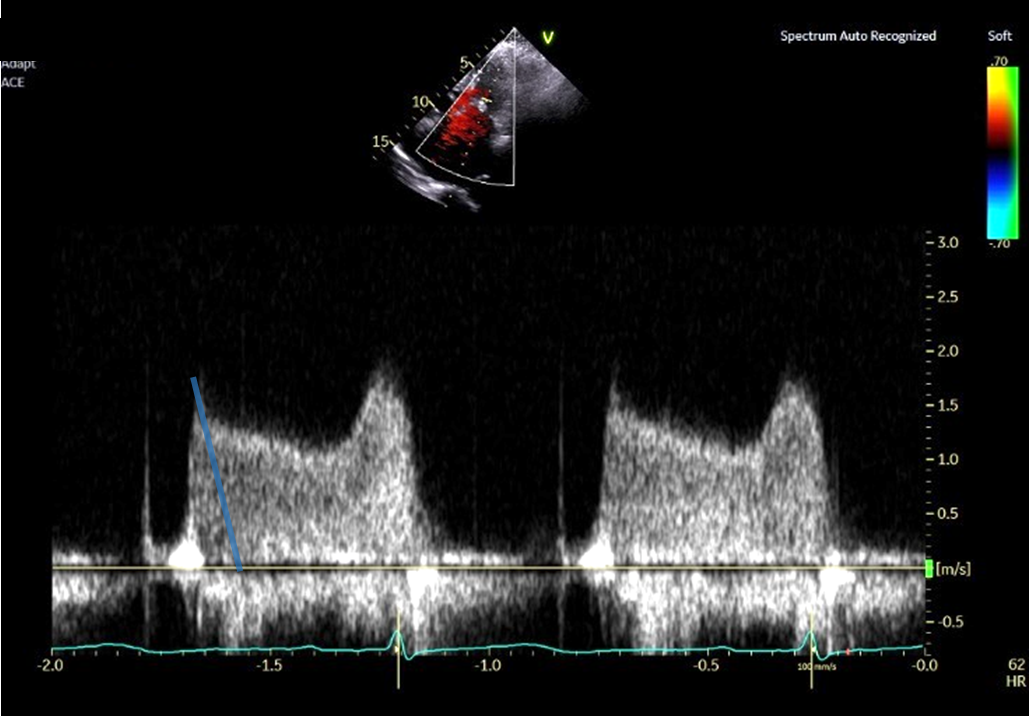

PHT法 拡張早期の急峻な部分から計測した場合 (No15_1)

PHT法 拡張早期の急峻な部分を避けて計測した場合 (No15_2)

① プラニメトリ法で僧帽弁口面積を計測する時相は収縮中期である

② 動画中の傍胸骨短軸断面において、僧帽弁交連部の癒合を認める

③ PHT法で弁口面積を求める際は、拡張早期の急峻な部分を避けて計測する

④ PHT法は僧帽弁狭窄をきたしていれば、リウマチ性、退行性のどちらでも使用することができる

⑤ 僧帽弁口面積を推定する方法である連続の式は、有意な大動脈弁逆流や僧帽弁逆流があっても使用することができる